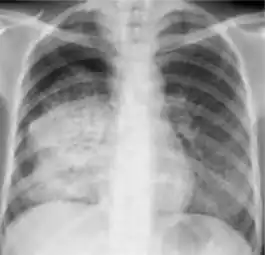

Chest X-ray

Tuberculosis creates cavities visible in x-rays like this one in the patient's right upper lobe.

A posterior-anterior (PA) chest X-ray is the standard view used; other views (lateral or lordotic) or CT scans may be necessary.

In active pulmonary TB, infiltrates or consolidations and/or cavities are often seen in the upper lungs with or without mediastinal or hilar lymphadenopathy.[1] However, lesions may appear anywhere in the lungs. In HIV and other immunosuppressed persons, any abnormality may indicate TB or the chest X-ray may even appear entirely normal.[1]